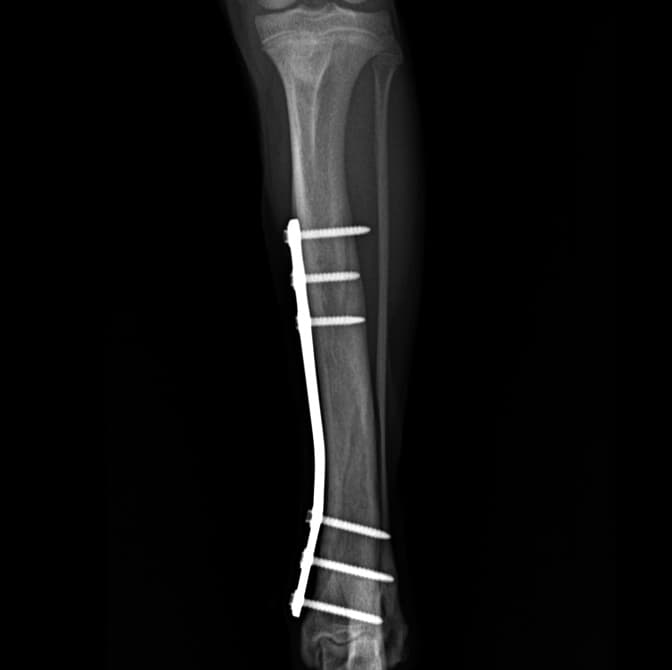

정형외과 전공의 수의사가 직접 수술합니다.

11유명한 Stryker사 장비. 골절 수술, 절골등 다양한 정형/신경외과 수술시 사용

12정교한 정형외과 도구를 사용하여 신속 정확한 정형외과 수술이 가능

13수술 중 골절 상태 혹은 이식물 적용 후 상태 등 육안으로 명확히 확인하기 힘든 상태를 X-ray 확인하여 정확한 수술 결과를 만들어 내는 것이 가능